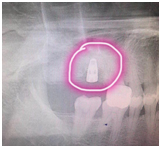

2018年9月7号上午,局部麻醉下与南部院区陈无名主任一起共同给患者做了上颌窦内提术、骨挤压术、种植牙手术,耗时半个小时完成,术后患者目前无不适症状,还跟医生开玩笑说也就像拔了一颗牙的感觉,没有想象中的恐怖!